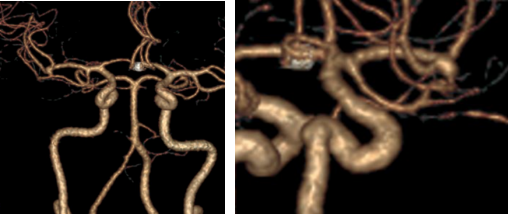

CTA(天坛医院2020-10-09)

全脑血管造影:右侧大脑中动脉M1分叉处动脉瘤,瘤体3.3 mm*4.1 mm,瘤颈2.7 mm。前交通动脉瘤栓塞完全。

全麻满意后,常规消毒铺巾,采用改良 Seldinger技术穿刺右侧股动脉成功,置入6F动脉鞘。黑泥鳅导丝带领5F单弯导管行脑动脉造影,右侧颈内动脉造影见:右侧大脑中动脉M1分叉处动脉瘤,瘤体3.3 mm*4.1 mm,瘤颈2.7 mm。前交通动脉瘤栓塞完全。